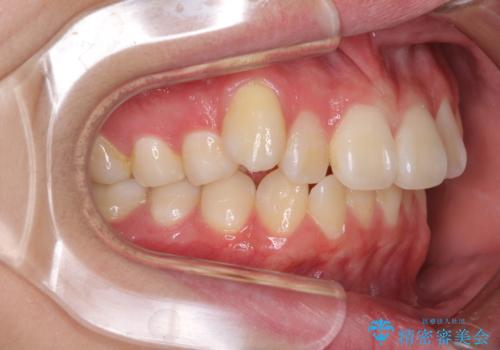

- 八重歯を気にして来院された高校生の患者様です。

ボディーコンタクトの激しい部活動を行っているため、補助装置とインビザラインを用いて、部活動を継続しながら治療を行うこととしました。

八重歯を効率よく改善するため、補助装置を使用して上顎の奥歯を後方に移動させました。

部活動をしながらでしたが、マウスピースをしっかりと装着してくださったので、1年半程度で終了することができました。